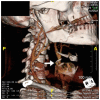

We present the case of a mixed martial arts (MMA) cage fighter who presented to the emergency department with a right sided common carotid artery pseudoaneurysm as a result of a neck trauma at an MMA event. We discuss the management of blunt force neck trauma, differential diagnosis, imaging findings and review the literature on blunt cerebrovascular injury following blunt force injury to the neck.